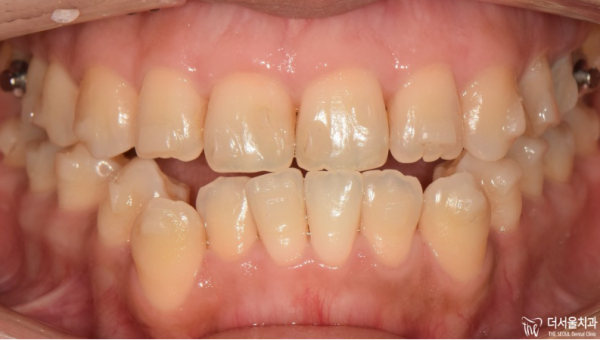

아래턱이 앞으로 돌출이되면서 정면에서 보면

반대교합이 확인됩니다.

입이 완전히 다물어지지 않는 상태로 일상에서도

많은 불편함이 있었을 듯 합니다.

The lower jaw protrudes forward, and when you look at it from the front

Opposite occlusion is confirmed.

I can't close my mouth completely. Even in my daily life

There must have been a lot of inconvenience.